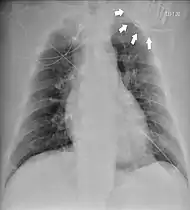

Chest radiograph showing twiddler's syndrome. The leads of the automated external defibrillator are wrapped around the device and can't be seen in the ventricle.

Twiddler's syndrome is a malfunction of a pacemaker due to manipulation of the device and the consequent dislodging of the leads from their intended location. As the leads move, they stop pacing the heart and can cause strange symptoms such as phrenic nerve stimulation resulting in abdominal pulsing or brachial plexus stimulation resulting in rhythmic arm twitching.[1] Twiddler's syndrome in patients with an implanted defibrilator may lead to inadequate, painful defibrillation-shocks.[2]